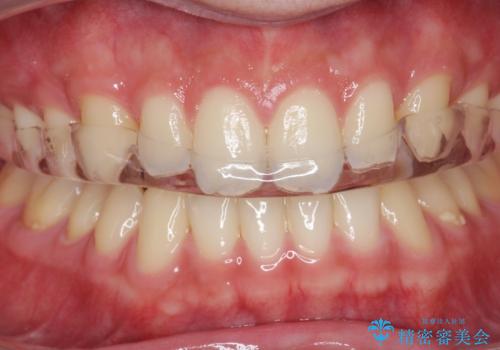

歯ぎしり・食いしばり・ナイトガード掲載症例数22件

最新 歯ぎしり・食いしばり・ナイトガード症例